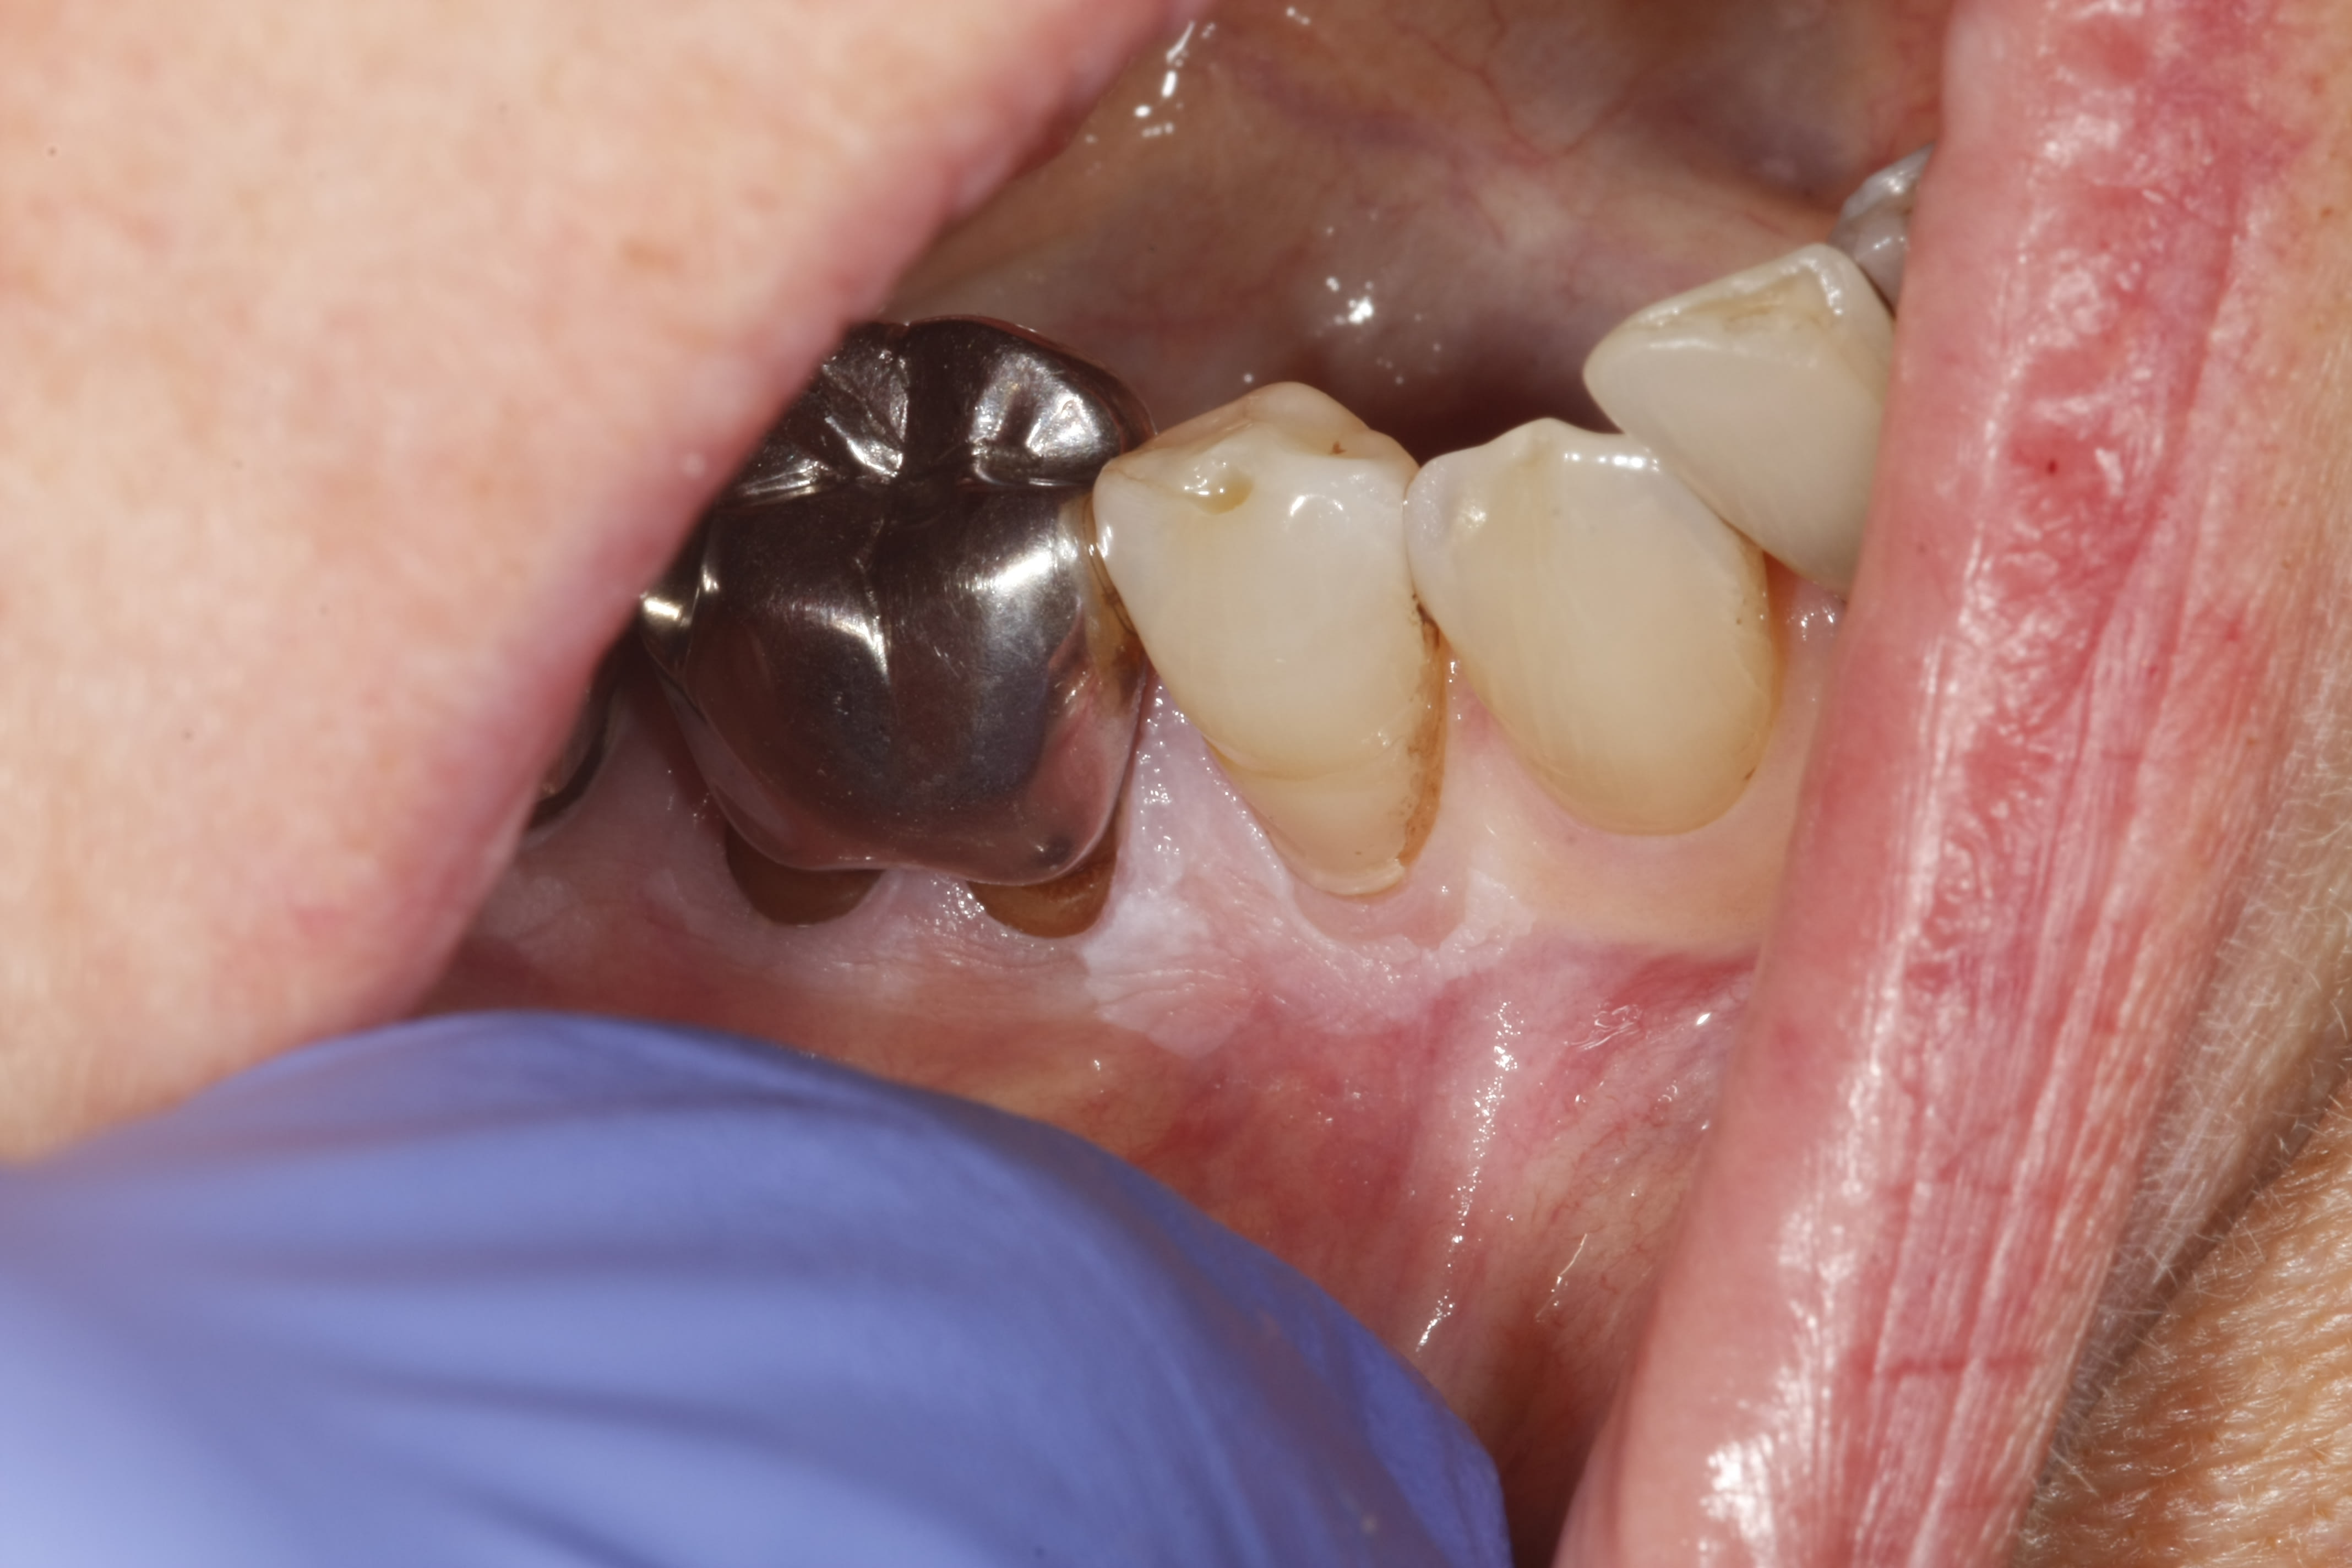

J'ai une charmante mamie de 84 ans avec une kératose chronique que j'ai du mal à identifier, et mes correspondants paro et stomato tout autant...

Lésion non détachable, apparue il y a 2 ans approximativement. L'étendue, la localisation varient peu au fil du temps. Les douleurs associées par contre, vont de "gêne" à "douloureux avec la brosse à dent 15/100ème" selon les moments.

Biopsie réalisée : Leucokératose isolée, sans malignité.

Dans les planches en cours de publication du Dr Lotfi Benslama et ses confrères, cela ressemble plus ou moins à :

Papillomatose orale floride

"L'âge de survenue des lésions est habituellement entre la sixième et la huitième décennie... La réalisation de biopsies multiples, fréquemment répétés, s'avère souvent nécessaire"